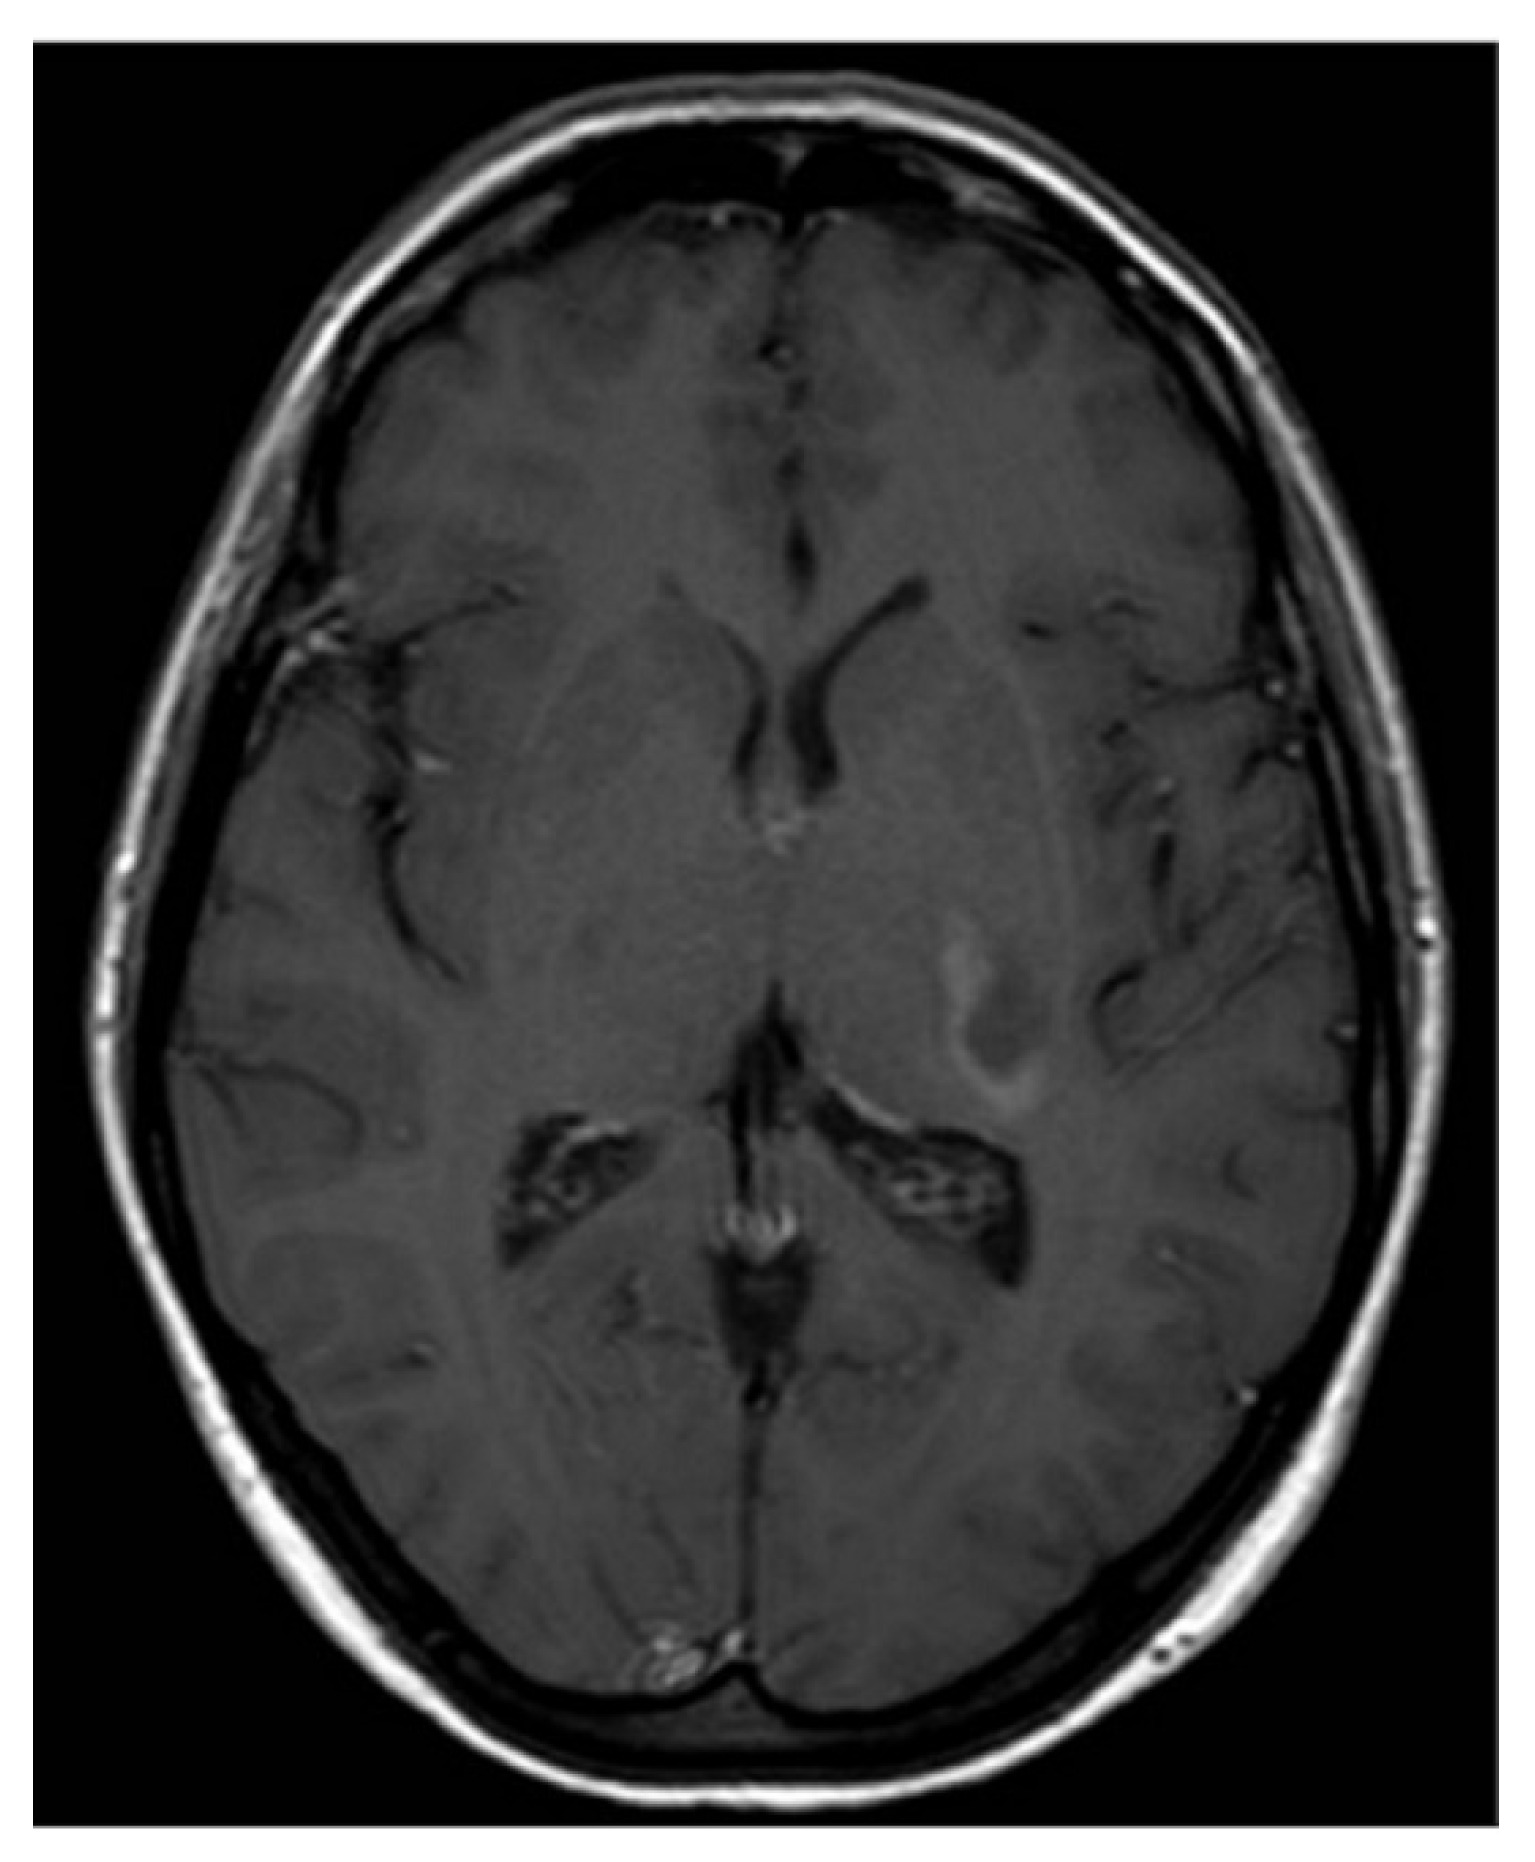

Subsequent magnetic resonance imaging (MRI) of the brain and C-spine revealed an area of hyperintense lesion on T2-weighted imaging involving the posterior limb of the internal capsule, adjacent to the left posterior thalamus with perilesional oedema (Figure 1 and Figure 2). Further hyperintensities were noted in the left frontotemporal region. These lesions demonstrated incomplete ring enhancement with gadolinium and facilitated diffusion restriction, consistent with acute demyelinating lesions. The lesions on the scan did not meet the MAGNIMS criteria for a multiple sclerosis diagnosis.

T2-weighted axial MRI.

Figure 2.

T1-weighted axial MRI post gadolinium.